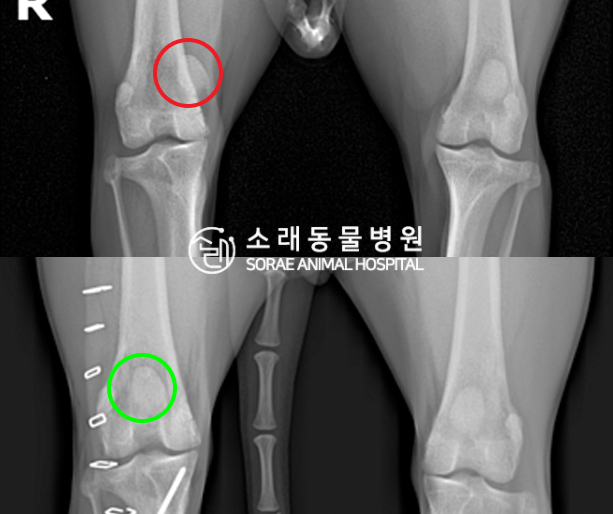

수술전과 수술후에 촬영한 아롱이의 슬개골

방사선 사진입니다. 나란히 놓고 비교해보니

슬개골의 위치에 확연한 차이가 있는 것을

확인해 볼 수 있는데요. 내측으로 탈구되어 있던

슬개골이 원래 제자리인 활차구에 예쁘게

자리 잡고 있는 모습을 확인할 수 있었습니다.